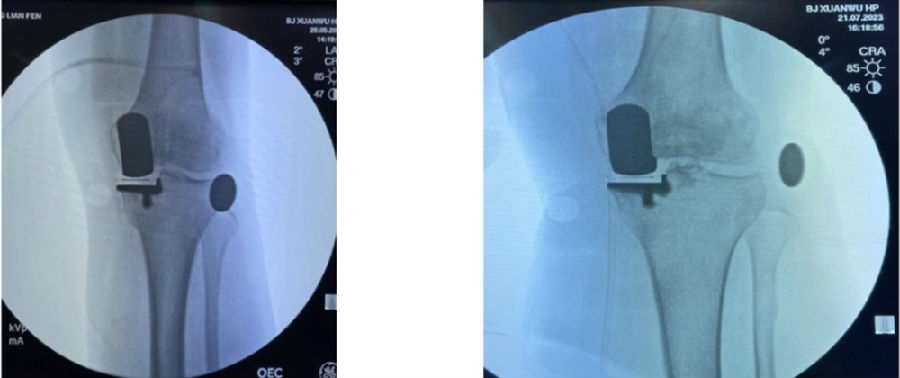

12、术后拍片

目前,笔者团队已经做了70多例,在早期探索过程中可能会出现一些问题,但是之后基本上都是比较好的,术后片子比较赏心悦目。

典型病例